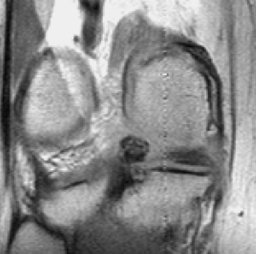

In this case arrows to highlight the abnormality are displayed only on user's request after the user clicks on description or diagnosis.

Case 4

5976.jpg (16246 bytes)6040.jpg (13715 bytes)

History

Description

Diagnosis